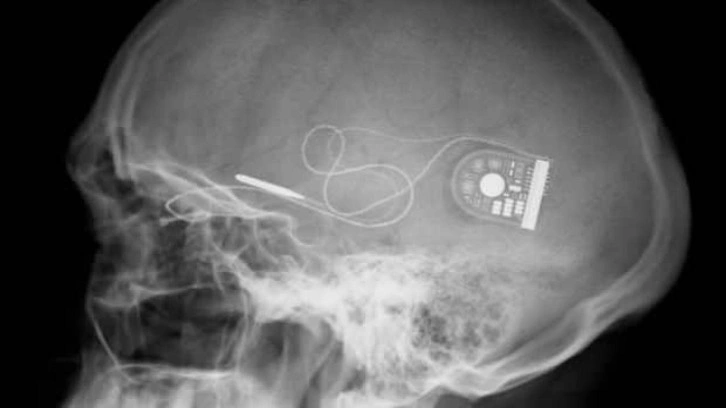

The Defense Advanced Research Projects Agency (DARPA), ABD ordusu için ileri teknoloji ürünler üretmekten sorumlu ABD Savunma Bakanlığı’na bağlı bir devlet kurumu. DARPA'ya son olarak ABD Savunma Bakanlığı tarafından bir askerin beynine yerleştirilecek ve anılarını kaydedecek implant geliştirme emri verildi. İmplant askerin beyninde adeta kara kutu olarak görev alacak. Asker bu implant ile hafıza kaybına uğrasa dahi implant bu anıları geri yükleyebilecek.

DARPA, konuyla ilgili olarak Medtronic gibi beyin implantları konusunda uzman ticari şirketlerden teklif bekliyor. Parkinson hastalığının etkilerini azaltmak için beyin implantları geliştiren Medtronic şirketi DARPA'nın bu teklifine sıcak bakıyor. Ayrıca IBM gibi büyük Ar-Ge bütçeleri olan şirketler de bu projeye katılmayı hedeliyor.